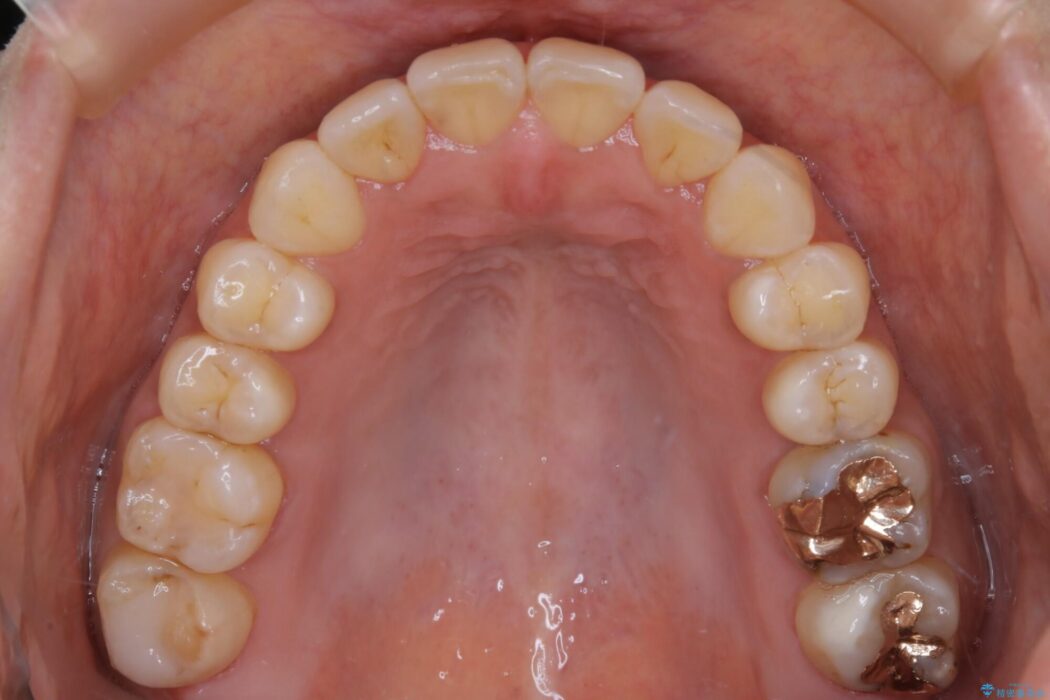

【20代女性】開咬の隙間と歯列の凸凹をまとめて改善する

なるべく非抜歯にて治療をするためインビザライン(マウスピース)とマイクロインプラントを併用した治療を行いました。

マウスピースとマイクロインプラントの併用により矯正するための隙間を確保し、治療期間は長くなりますが非抜歯できれいな歯列弓を得ることができます。